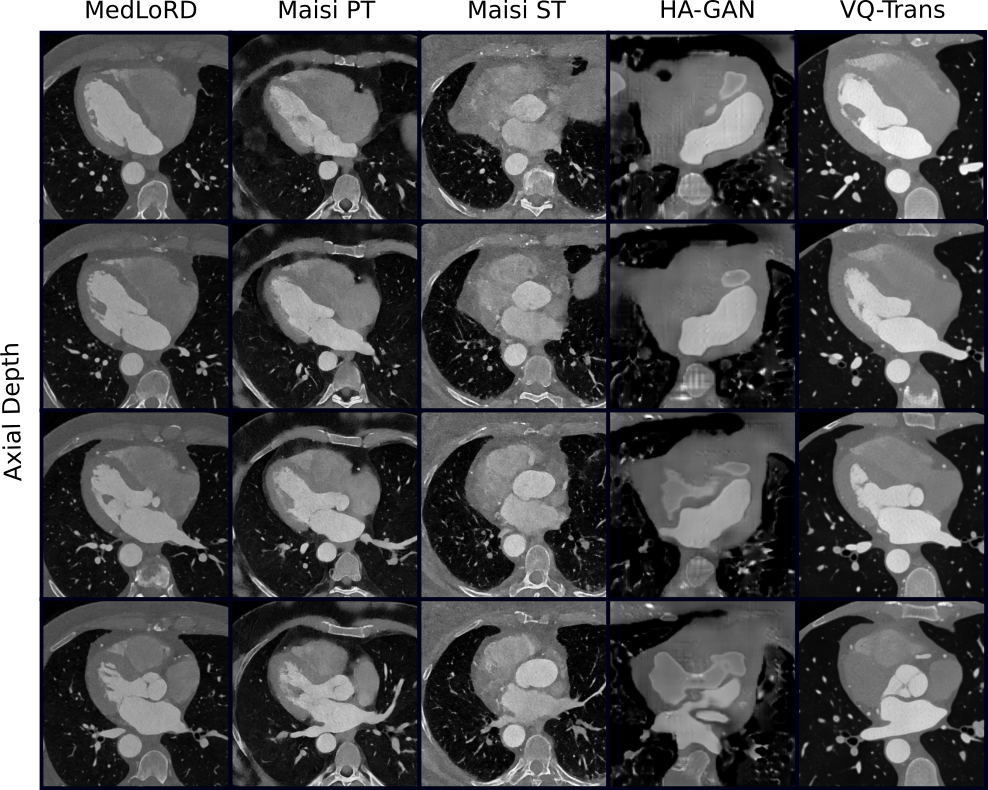

First, we conducted unconditional image synthesis. Fig. 2 shows representative samples from both the PCCTA and LUNA datasets. MedLoRD consistently generates high-quality, realistic images, preserving both global and local structural details. In contrast, other models exhibited unstable behavior, with some samples showing poor quality and heavy artifacts (e.g., loss of heart structures in MAISIST, poor realism in HA-GAN; see Fig. 2(a)). VQ-Trans and MAISIPT showed partial success, though the latter still displayed artifacts in PCCTA samples.

Refer to caption

Figure 2: Randomly selected unconditional samples for each method. Additional MedLoRD samples are provided in the supplementary material.

(a) Randomly selected unconditional PCCTA samples (axial view).